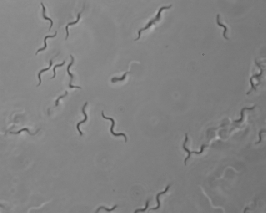

クレブシエラ・ニューモニエ(Klebsiella pneumoniae) バクテリア

クレブシエラ・ニューモニエは、グラム陰性の桿菌で、日本では肺炎桿菌とも呼ばれます。口腔や腸管における常在菌で、環境中からも検出されます。

しばしば呼吸器感染症、尿路感染症などを引き起こし、弱毒菌ですが、菌交代現象を起こし、感染症を引き起こし問題となります。

クレブシエラ種は水、土壌、動物などの自然界に遍在しており、医療機器や医療環境に定着する可能性があります。